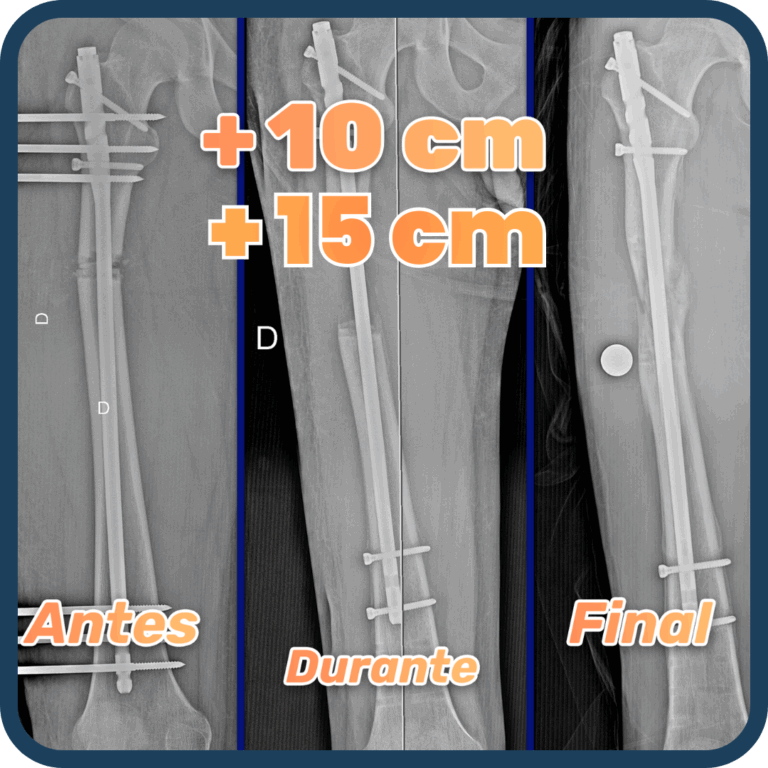

En la cirugía de alargamiento óseo se realiza el método LON, el cual permite reducir el tiempo de permanencia del fijador externo (HMC). El procedimiento consiste en realizar una fractura controlada en el hueso (fémur o tibia). Luego, se coloca un clavo endomedular dentro del hueso , junto al fijador externo HMC que es unido a la extremidad, gracias a agujas percutáneas llamados Schantz. Nuestra cirugía de alargamiento óseo, suele durar 2 horas aproximadamente. La hospitalización alrededor de 5 días, para seguidamente continuar con el plan de recuperación preparado por Arthrosalud.